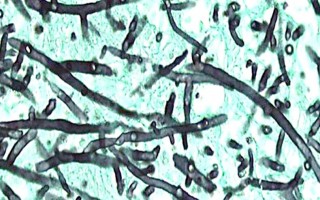

Patient diagnosed with black fungus at DMCH

United News of Bangladesh. Dhaka | Updated at 10:44pm on June 14, 2021

A patient was diagnosed with black fungus at Dhaka Medical College Hospital in Bangladesh's capital Dhaka on Monday, the hospital director said. DMCH director Brigadier...